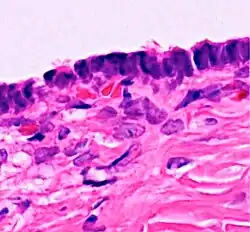

![]() | Carcinoma in situ | CIN-III (HSIL) showing diffuse severe atypia with loss of maturation involving full thickness of epithelium with intact basement membrane. | Category: Histopathology of carcinomas in situ | Carcinoma in-situ |